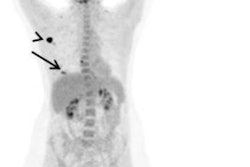

The company started a program that allowed participants to undergo PET/CT, noncontrast brain and pelvis MRI, and abdominal ultrasound exams every two years over a 10-year timespan. Employees could also undergo annual screenings such as chest x-ray, upper gastrointestinal x-ray with oral contrast, fecal occult blood test, prostate-specific antigen testing (for men over 55), and mammography (for women over 40). The program cost $1,350 per employee every two years; this cost was split between the company and participants.

For the imaging exams, employees were categorized into full participation (five screenings), partial (more than once and less than five), and no participation groups. Anzai's team measured the cancer detection rate, rate of cancer-related death, and cancer-related costs of care. Of 1,213 employees, 543 were full participants, 318 were partial, and 352 did not participate in the imaging protocol. Across all three groups, 54 cancers were identified, with the majority in the full and partial participation groups being early stage (0 to 1).